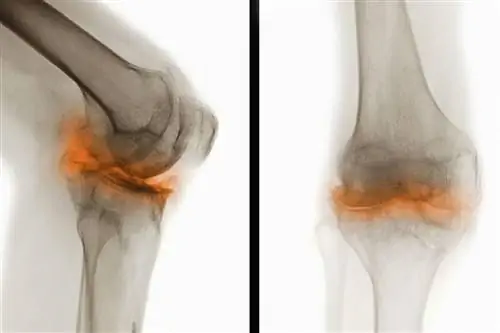

Рентгеновские снимки показывают тяжелый остеоартрит в колене.